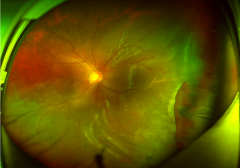

被足球击中右眼后眼球正在萎缩,一台联合手术保住眼睛

如果眼部受伤较严重,眼部皮肤出现破损,甚至有尖锐的物体扎到眼睛,眼内有内容物流出时千万要冷静。不要强行将眼内的异物取出,不要将流出的眼内容物推回眼内,不要用水冲洗...